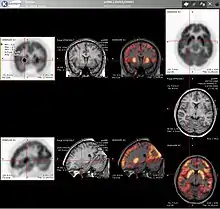

Neurology

PET imaging with oxygen-15 indirectly measures blood flow to the brain. In this method, increased radioactivity signal indicates increased blood flow which is assumed to correlate with increased brain activity. Because of its 2-minute half-life, 15O must be piped directly from a medical cyclotron for such uses, which is difficult.[15]

PET imaging with 18F-FDG takes advantage of the fact that the brain is normally a rapid user of glucose. Standard 18F-FDG PET of the brain measures regional glucose use and can be used in neuropathological diagnosis.

Brain pathologies such as Alzheimer's disease greatly decrease brain metabolism of both glucose and oxygen in tandem. Therefore 18F-FDG PET of the brain may also be used to successfully differentiate Alzheimer's disease from other dementing processes, and also to make early diagnoses of Alzheimer's disease. The advantage of 18F-FDG PET for these uses is its much wider availability. Some 18F based radioactive tracers used for Alzheimer's include florbetapir, flutemetamol, PiB and florbetaben, which are all used to detect amyloid-beta plaques (a potential biomarker for Alzheimer's) in the brain.[16]

PET imaging with FDG can also be used for localization of seizure focus. A seizure focus will appear as hypometabolic during an interictal scan.[17] Several radiotracers (i.e. radioligands) have been developed for PET that are ligands for specific neuroreceptor subtypes such as [11C] raclopride, [18F] fallypride and [18F] desmethoxyfallypride for dopamine D2/D3 receptors, [11C] McN 5652 and [11C] DASB for serotonin transporters, [18F] Mefway for serotonin 5HT1A receptors, [18F] Nifene for nicotinic acetylcholine receptors or enzyme substrates (e.g. 6-FDOPA for the AADC enzyme). These agents permit the visualization of neuroreceptor pools in the context of a plurality of neuropsychiatric and neurologic illnesses.

PET may also be used for the diagnosis of hippocampal sclerosis, which causes epilepsy. FDG, and the less common tracers flumazenil and MPPF have been explored for this purpose.[18][19] If the sclerosis is unilateral (right hippocampus or left hippocampus), 18F-FDG uptake can be compared with the healthy side. Even if the diagnosis is difficult with MRI, it may be diagnosed with PET.[20][21]